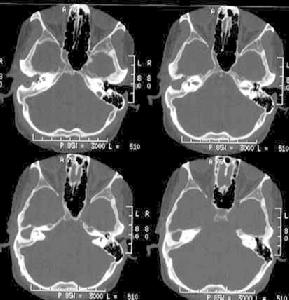

乳突一般可檢查血象、乳突相或加膿液細菌培養加藥敏,需行乳突鑿開術者可選擇檢查框限“A”及“B”,疑顱內併發症可選擇“C”。中耳炎鼓膜穿孔流膿後症狀體徵反而加重者,多為突感染所致。乳突X線攝片或CT掃描,可見乳突區混濁或有骨質破壞.聽力學檢查及X線檢查雖有助於診斷,但並不具有特異性,而CT檢查無論是對診斷或對手術治療均有指導意義。本病多由急性化膿性中耳炎發展而來,及早使用足量有效抗生素是治療及預防本病關鍵,若保守治療2-3天炎症未能控制,乳突骨質有破壞,可能發生其他併發症時應立即行單純乳突鑿開術。

乳突中耳炎鼓膜穿孔流膿後症狀體徵反而加重者多為突感染所致。乳突X線攝片或CT掃描,可見乳突區混濁或有骨質破壞